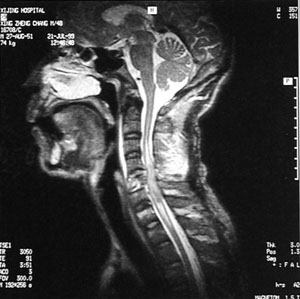

椎動脈脈衝都卜勒頻譜形態椎動脈脈衝都卜勒頻譜形態在收縮中期血流速度瞬時驟降,形成收縮期雙峰,第一峰高尖,第二峰圓鈍,兩峰之間形成切跡,可早期提示SSS。在影像學檢查中,DSA目前仍是SSS診斷的金標準,但其對血流動力學評價是困難的;MRA越來越多地用於SSS診斷,可以清晰顯示血管內徑及走行,觀察管腔狹窄或閉塞程度,也可顯示血流方向,但其價格昂貴,不易觀察其血流速度和血流量等;TCD診斷鎖骨下動脈盜血綜合徵具有直觀、快捷、準確、易於早期發現的優點,結合二維及彩色都卜勒超聲可以明確鎖骨下動脈盜血綜合徵的病因、病變部位及程度。使其成為臨床SSS診斷及病因判斷的可信賴的檢查方法。

主動脈縮窄SSS確診主要靠腦血管造影,為避免血管造影時引起椎動脈起始段功能性狹窄,有條件的地方,最好行全腦血管造影以明確診斷。經股動脈穿刺腦血管及患側上肢血管造影可明確閉塞部位,有利於外科手術治療。對於急性鎖骨下動脈閉塞者,最好於閉塞後3天內行取栓術,有利於血液再通,避免再次栓塞。本組1例取栓術後至今已4年,配合抗凝治療,未再出現缺血症狀。大多數作者對SSS手術治療有較好的評價,鎖骨下與頸總動脈架橋術,是治療本症最常用的方法。對於少數長期狹窄的SSS患者且無急性腦損害者,尤其是壯年患者,可試用抗血小板聚集劑(6個月或以上)以及病因治療觀察。經顱多普超聲(TCD)可以連續及動態觀察椎動脈、基底動脈血流方向和速度,觀察顱內其他動脈被盜血的影響程度,是盜血綜合徵的敏感指標,可以評價治療效果和隨診。